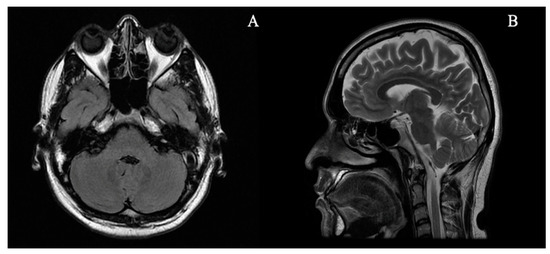

2. Case Report